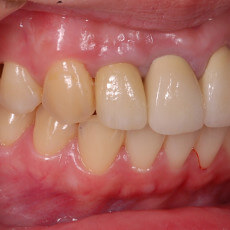

門牙牙套失敗後的植牙重建

對於已經被拔除的牙齒,人工植牙是目前為止最佳的重建方式,她不但可以恢復喪失的咀嚼功能,同時讓鄰牙不必為了做牙橋而受到傷害.以下為植牙的流程介紹.